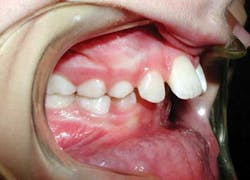

Young children (ages 6–10) with severely protruded upper front teeth, commonly called “buck teeth,” are at increased risk for dental trauma and may benefit from an orthodontic correction, according to a study published recently in the American Journal of Orthodontics & Dentofacial Orthopedics. (1) The study found that approximately 1 in 3 children who were treated for severely protruding teeth were less likely to experience dental trauma (such as a chipped, broken, or knocked out permanent tooth).

“Protruding front teeth cause other problems for children. The ‘bite’—the manner in which the upper and lower teeth meet—may be improper, and make it difficult for a child to bite food or to chew properly. The condition can interfere with speech for some individuals. And there’s an emotional toll, too, for children who may be bullied because of their teeth,” says Dr. Poole. “Interceptive treatment addresses the immediate protrusion problem. Parents need to know that most patients will require a second phase of treatment after most or all of their permanent teeth are in to move teeth into their final, optimal positions.”

“Parents should also understand that children go through what we call an ‘ugly duckling’ phase, when permanent teeth begin to emerge and seem too large or appear to be spaced incorrectly,” Dr. Poole says. “Most children will ‘grow into’ their teeth and go through this phase without the need for orthodontic treatment. But for those children whose teeth protrude significantly, I recommend parents take their child to an orthodontist for an evaluation.”